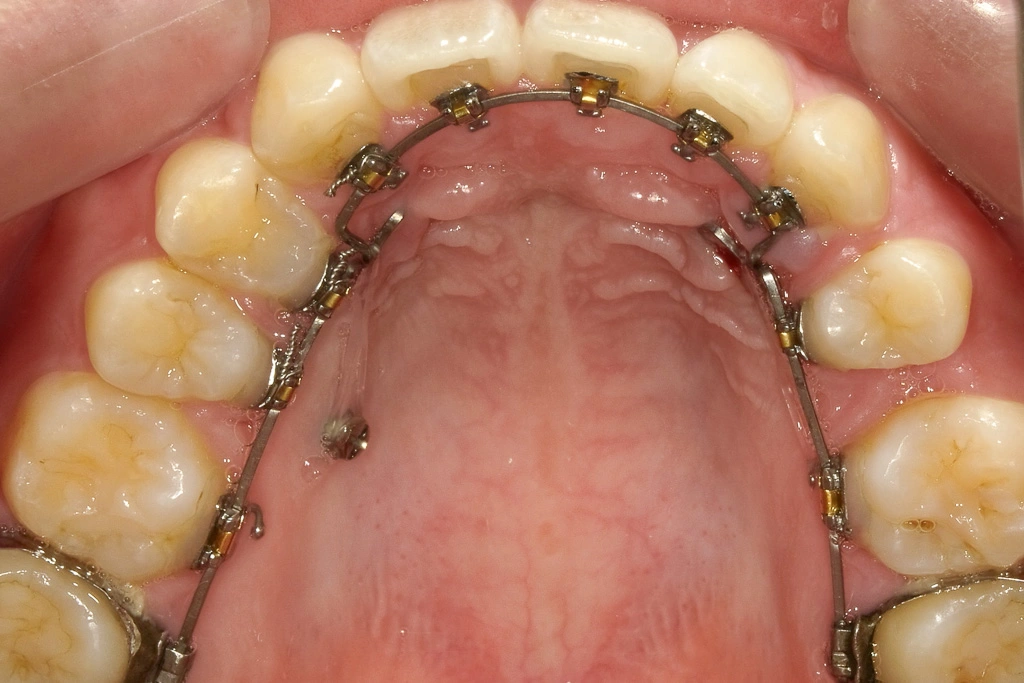

「ワイヤーだけど目立たない装置で」

マウスピースタイプはしっかり使えるか不安とのことで、上の歯は裏側の装置を用いました。

アンカースクリューでも歯の位置を調整しています

元々の歯の本数が左右で異なっているため、抜歯している部位が違います。左右差を整えるためにアンカースクリューにて調整しています。